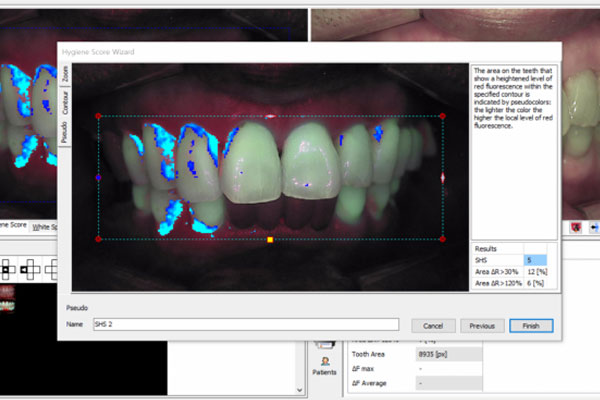

원인을 제대로 찾지 못하면 치료가 길어집니다. AI 기술이 적용된

첨단 장비를 통해 잇몸병의 원인을 꼼꼼하게 분석합니다.

AI 리포트를 활용해 잇몸병 원인에 맞는 예방 및 치료 계획을 세웁니다.